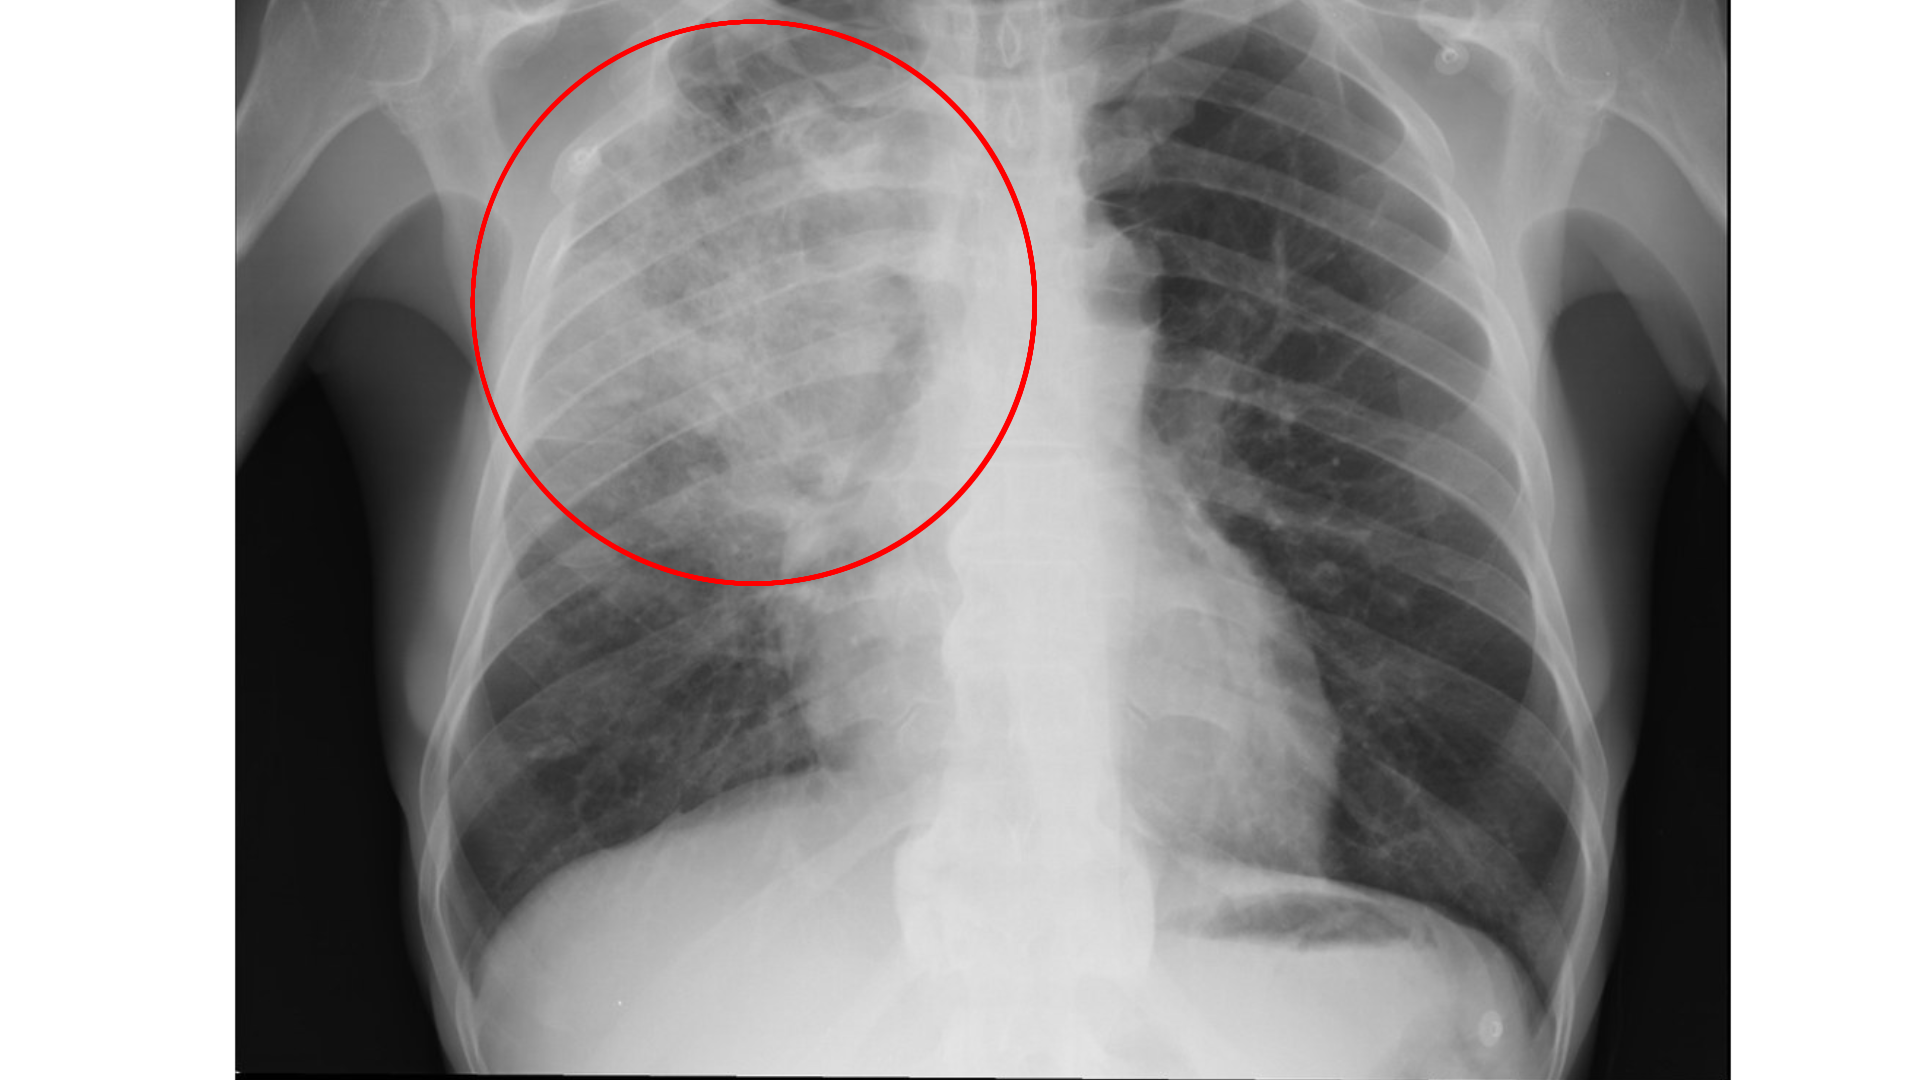

폐렴, 방심하다간 큰코다친다

나이가 들수록 폐렴은 단순한 감기를 넘어 생명을 위협하는 질병이 될 수 있습니다. 면역력이 약해진 노년층에게 폐렴은 감기 이후 합병증으로 찾아오기도 하지만, 아무런 전조 증상 없이 갑자기 발생해 심각한 호흡곤란을 유발하기도 합니다. 특히 만성질환(심장 질환, 폐 질환, 당뇨, 신장 질환 등)을 앓고 있는 분들에게는 입원 치료를 넘어 사망에 이르게 하는 치명적인 질환입니다.